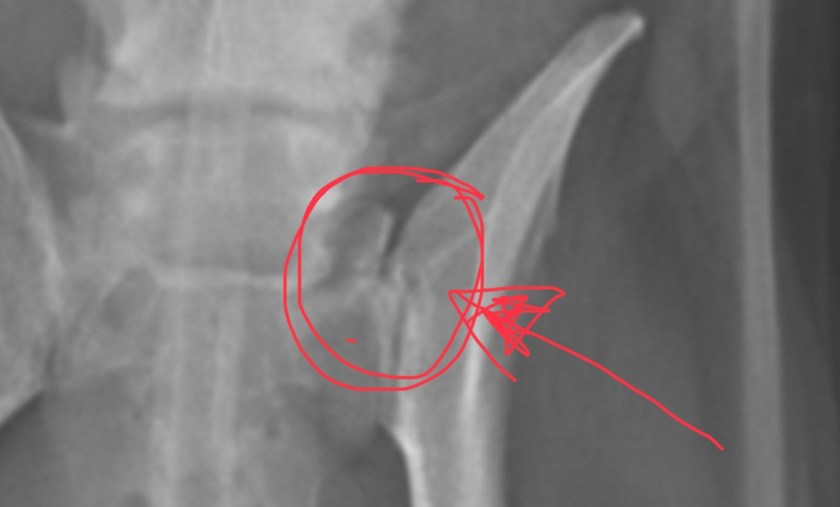

Ek is kwaad, hartseer, alles in een. My jongste Miniatuur Schnauzer is ernstig beseer en ek weer nie hoe of wanneer nie. Laat ek dan probeer om dit uit te klaar.